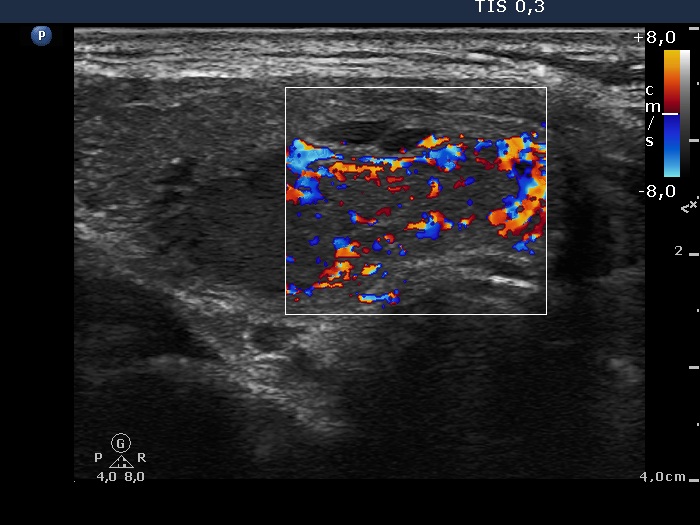

Consecutively operated patients with autoimmune thyroid disease - case 50 (408) (ultrasonographic picture 7)

Lower part of the right lobe, another longitudinal view, color Doppler mode.